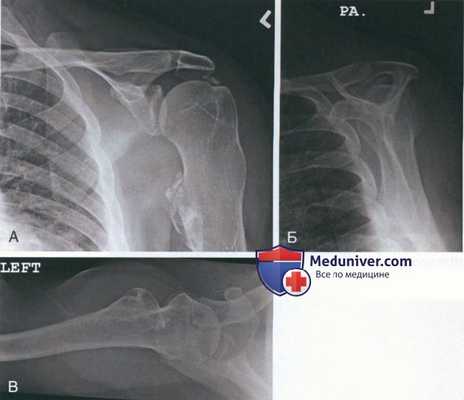

Рисунок 6 Рисунок 1

- С помощью спинальной иглы локализуются депозиты кальция (рис. 6)

- Первичное предоперационное обследование и рентгенограммы в трех проекциях (см. рис. 1, A-В) должны помочь локализовать депозиты в трех плоскостях

Рисунок 1

- Первичное рентгенологическое обследование должно включать рентгенограммы в трех проекциях: передне-задней, Y-лопаточной и подмышечной:

• Передне-задние проекции (рис. 1, А):

- Нейтральная ротация

- Внутренняя ротация: позволяет увидеть депозиты в сухожилиях подостной и малой круглой мышц

- Наружная ротация: позволяет увидеть депозиты в сухожилии надостной мышцы

• Y-лопаточная проекция: помогает оценить, является ли кальцифицирующий тендинит причиной импинджмента (см. рис. 1, Б)

• Подмышечная проекция: визуализирует депозиты в сухожилии подлопаточной мышцы (см. рис. 1, В)

• Дополнительная надостная проекция помогает увидеть признаки импинджмента

• Три проекции плечевого сустава позволят точно локализовать патологическое изменения в трех плоскостях и являются частью предоперационного планирования (стрелки на рис. 1, A-В указывают на депозиты кальция)